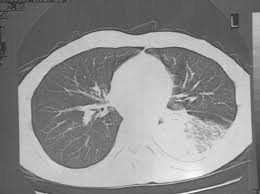

Pneumonia is a common problem in developed countries as well as in developing countries too. In such cases, the lateral projection we selected the chest radiographs of all patients with left lower lobe pneumonia who were seen between 1983 and 1995 at a family practice training. It is one of three anatomic classifications of pneumonia. The images show a density posteriorly in the left lower lobe. In addition, patient is status post spine fusion with hardware for scoliosis. For example, pneumonia of left lower lobe is coded to 486. Recurrent left lower lobe pneumonia in a. For instance a lobar pneumonia caused by streptococcus pneumoniae may become diffuse if the patient does not respond to the treatment. It really depends on the type and extent of the pneumonia. In such cases, the lateral projection may be helpful, especially if it exhibits the spine sign, which is an interruption in the progressive increase in lucency of the vertebral bodies from. Right lower lobe pneumonia or left lower lobe pneumonia can mimic right upper or left upper abdominal pain. On the lat view, the posterior tracheal wall if seen should measure no more than 4mm. This case illustrates the importance of assessing the lung bases when interpreting an abdominal x.

The images show a density posteriorly in the left lower lobe. Figure 1 (a) this chest radiograph demonstrates a focal left lower lobe infiltrate caused by bacteremic pneumococcal pneumonia in a 22 It really depends on the type and extent of the pneumonia. The neutrophilic infiltrate is chiefly around the centre of the bronchi. Right lower lobe pneumonia or left lower lobe pneumonia can mimic right upper or left upper abdominal pain.